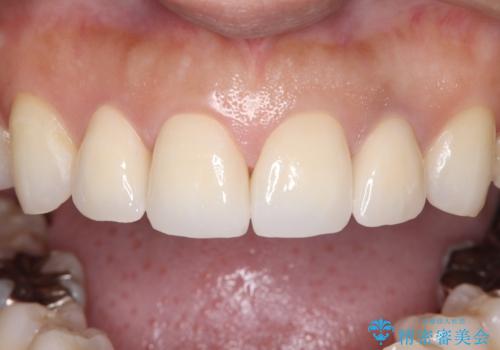

緻密な色合わせと形態調整を重ねた結果、長年のコンプレックスであった前歯の欠けや変色が解消。機能性と審美性が完璧に調和した、自信を持って笑える美しい口元を実現することができました。